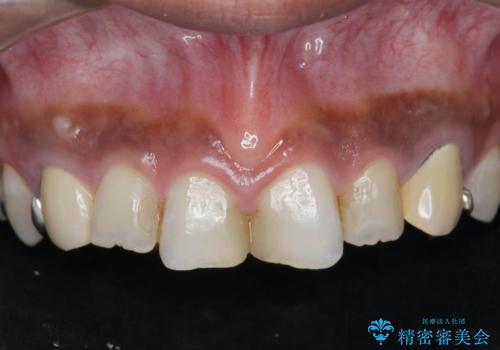

[ 歯ぐきから出血をする ] 歯周外科を伴うセラミックやりかえ治療